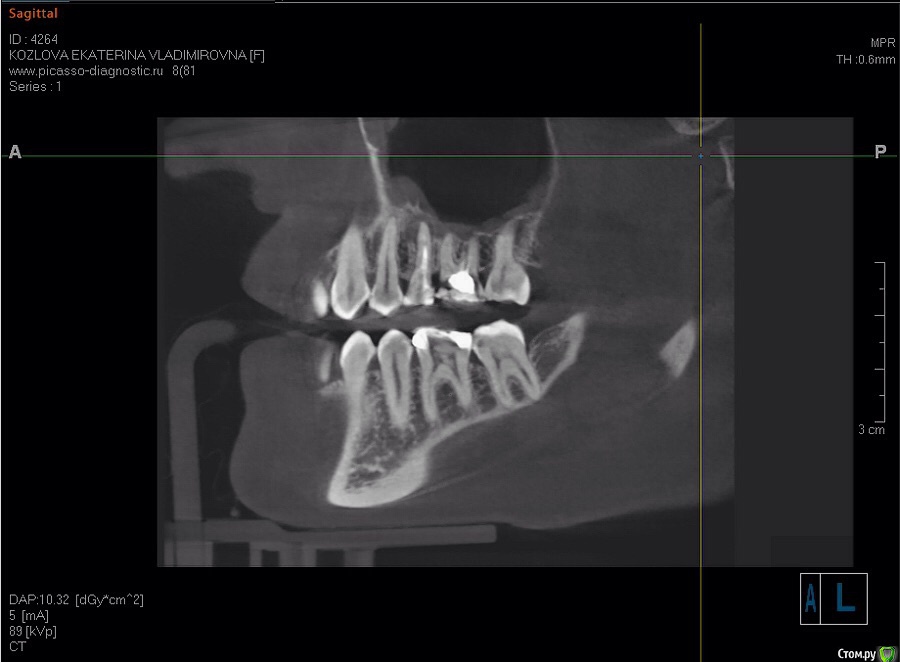

katrin12098 Опубликовано 15 августа, 2015 Поделиться Опубликовано 15 августа, 2015 (изменено) Здравствуйте!Подскажите пожалуйста.Заболела верхняя пятерка,пошла на прием к стоматологу сделали снимок сказали киста и нужно удалять в стационаре,так как зуб находиться рядом с гайморовой пазухой в поликлинике удалять отказались. Пропила пять дней амоксиклав зуб перестал беспокоить, насколько велика вероятность перфорации гайморовой пазухи и возможно ли удалить в клинике или всё же лучше обратиться в больницу в челюстно лицевую хирургию и удалить там? и какие могут быть осложнения? и возможно ли сохранить зуб? Изменено 15 августа, 2015 пользователем katrin12098 Ссылка на комментарий

katrin12098 Опубликовано 16 августа, 2015 Автор Поделиться Опубликовано 16 августа, 2015 Ходила на консультацию к двум хирургам и к члх в нии лор без лишних объяснений и разговоров сказали удалять(в меди сказали что нужно сделать кт пятого и шестого и после этого только возможно подумать над лечением..после удаления нижнего шестого с той же кистой паника и страх., Ссылка на комментарий

katrin12098 Опубликовано 19 августа, 2015 Автор Поделиться Опубликовано 19 августа, 2015 (изменено) Верхнюю пятерку решила удалять.подскажите что делать с шестым верхним?также интересует правая сторона пятый и шестой верхний зуб.возможна ли имплантация шестого нижнего и нужен ли костный блок? Изменено 19 августа, 2015 пользователем katrin12098 Ссылка на комментарий

IvanK Опубликовано 20 августа, 2015 Поделиться Опубликовано 20 августа, 2015 Вам же посоветовали Врача? по данным срезам нельзя сказать нужен ли костный блок? Ссылка на комментарий